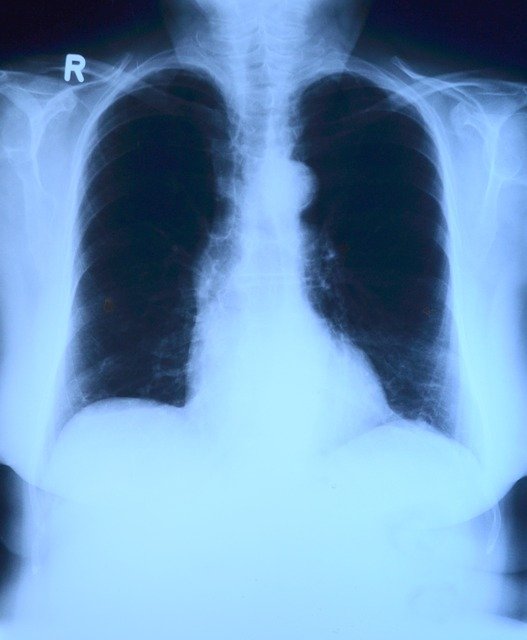

이번에 지정받은 특발성 폐섬유증은 원인을 알 수 없는 폐 염증 과정에서 섬유세포가 과증식해 폐 조직의 섬유화를 유발하고, 이로 인해 폐 기능이 급격히 저하돼 심하면 사망에 이르는 희귀 질환이다. 매년 10만명 당 100명 이하 꼴로 발병하며, 호흡곤란 등 일상생활이 어려운 증상을 보이지만 대증요법 외엔 효과적인 치료법이 없다.